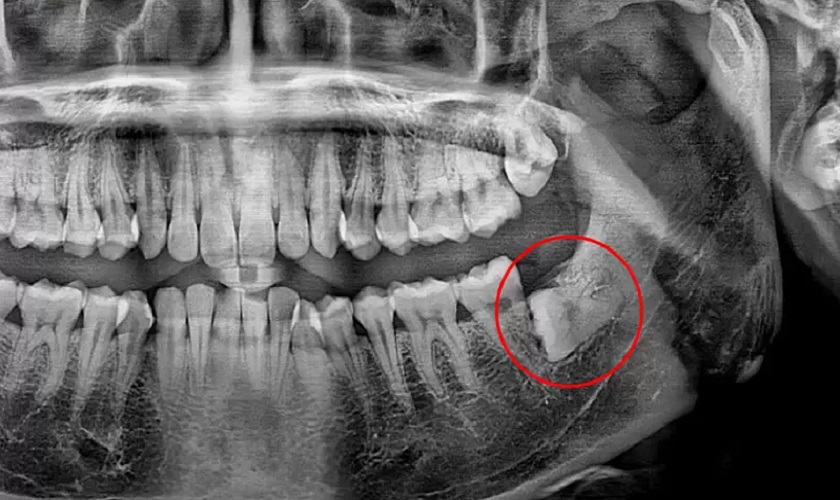

Không mọc răng khôn: Trường hợp này vẫn có răng khôn nhưng chúng nằm ẩn sâu dưới xương hàm, không nhô lên trên bề mặt nướu hoặc do bờ nướu quá dày làm răng không đủ khả năng trồi lên. Bởi vậy mà khách hàng không phát hiện ra chiếc răng khôn của mình.

Răng khôn có thể nằm ẩn trong xương hàm